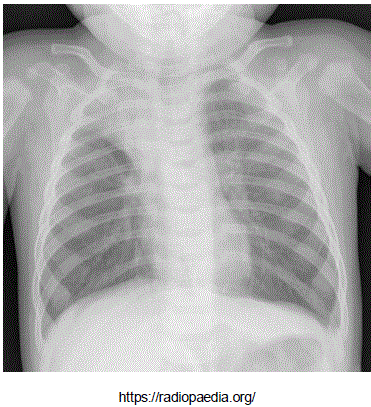

Adolescente masculino, 13 anos de idade, portador de anemia falciforme em seguimento regular com hematologista, apresenta queixa de febre e tosse há dois dias e dor em face anterior do tórax a direta. Ao exame clínico encontra-se em regular estado geral, levemente descorado, FC: 84 bpm, FR: 34 ipm, Saturação de Oxigênio: 95% em ar ambiente, Temp: 38°C, PA: 100/60 mmHg. Realizou radiografia de tórax, que mostrou a imagem abaixo:

enunciado 1543322-1

A conduta inicial mais adequada é: